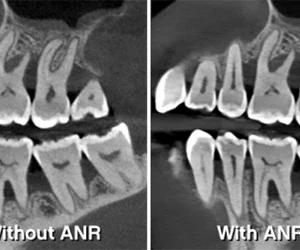

3D SLIKE NISKE BUKE U VISOKOJ REZOLUCIJI

Na 75 mikrona,

CS 8200 pruža 3D slike ultra visoke rezolucije

koje su idealne za endodontske primjene. U isto vrijeme, ANR algoritam smanjuje buku slike uz očuvanje kliničkih detalja.